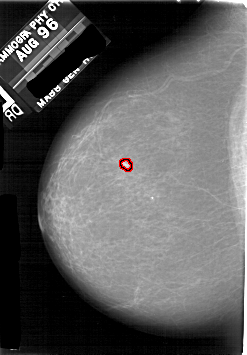

A_1731_1.LEFT_MLO

LEFT_MLO LINES 5206 PIXELS_PER_LINE 3706 BITS_PER_PIXEL 12 RESOLUTION 43.5 OVERLAY

FILE: A_1731_1.LEFT_MLO.OVERLAY

TOTAL_ABNORMALITIES 1

ABNORMALITY 1

LESION_TYPE CALCIFICATION TYPE PLEOMORPHIC DISTRIBUTION CLUSTERED

ASSESSMENT 4

SUBTLETY 2

PATHOLOGY MALIGNANT

TOTAL_OUTLINES 1

BOUNDARY